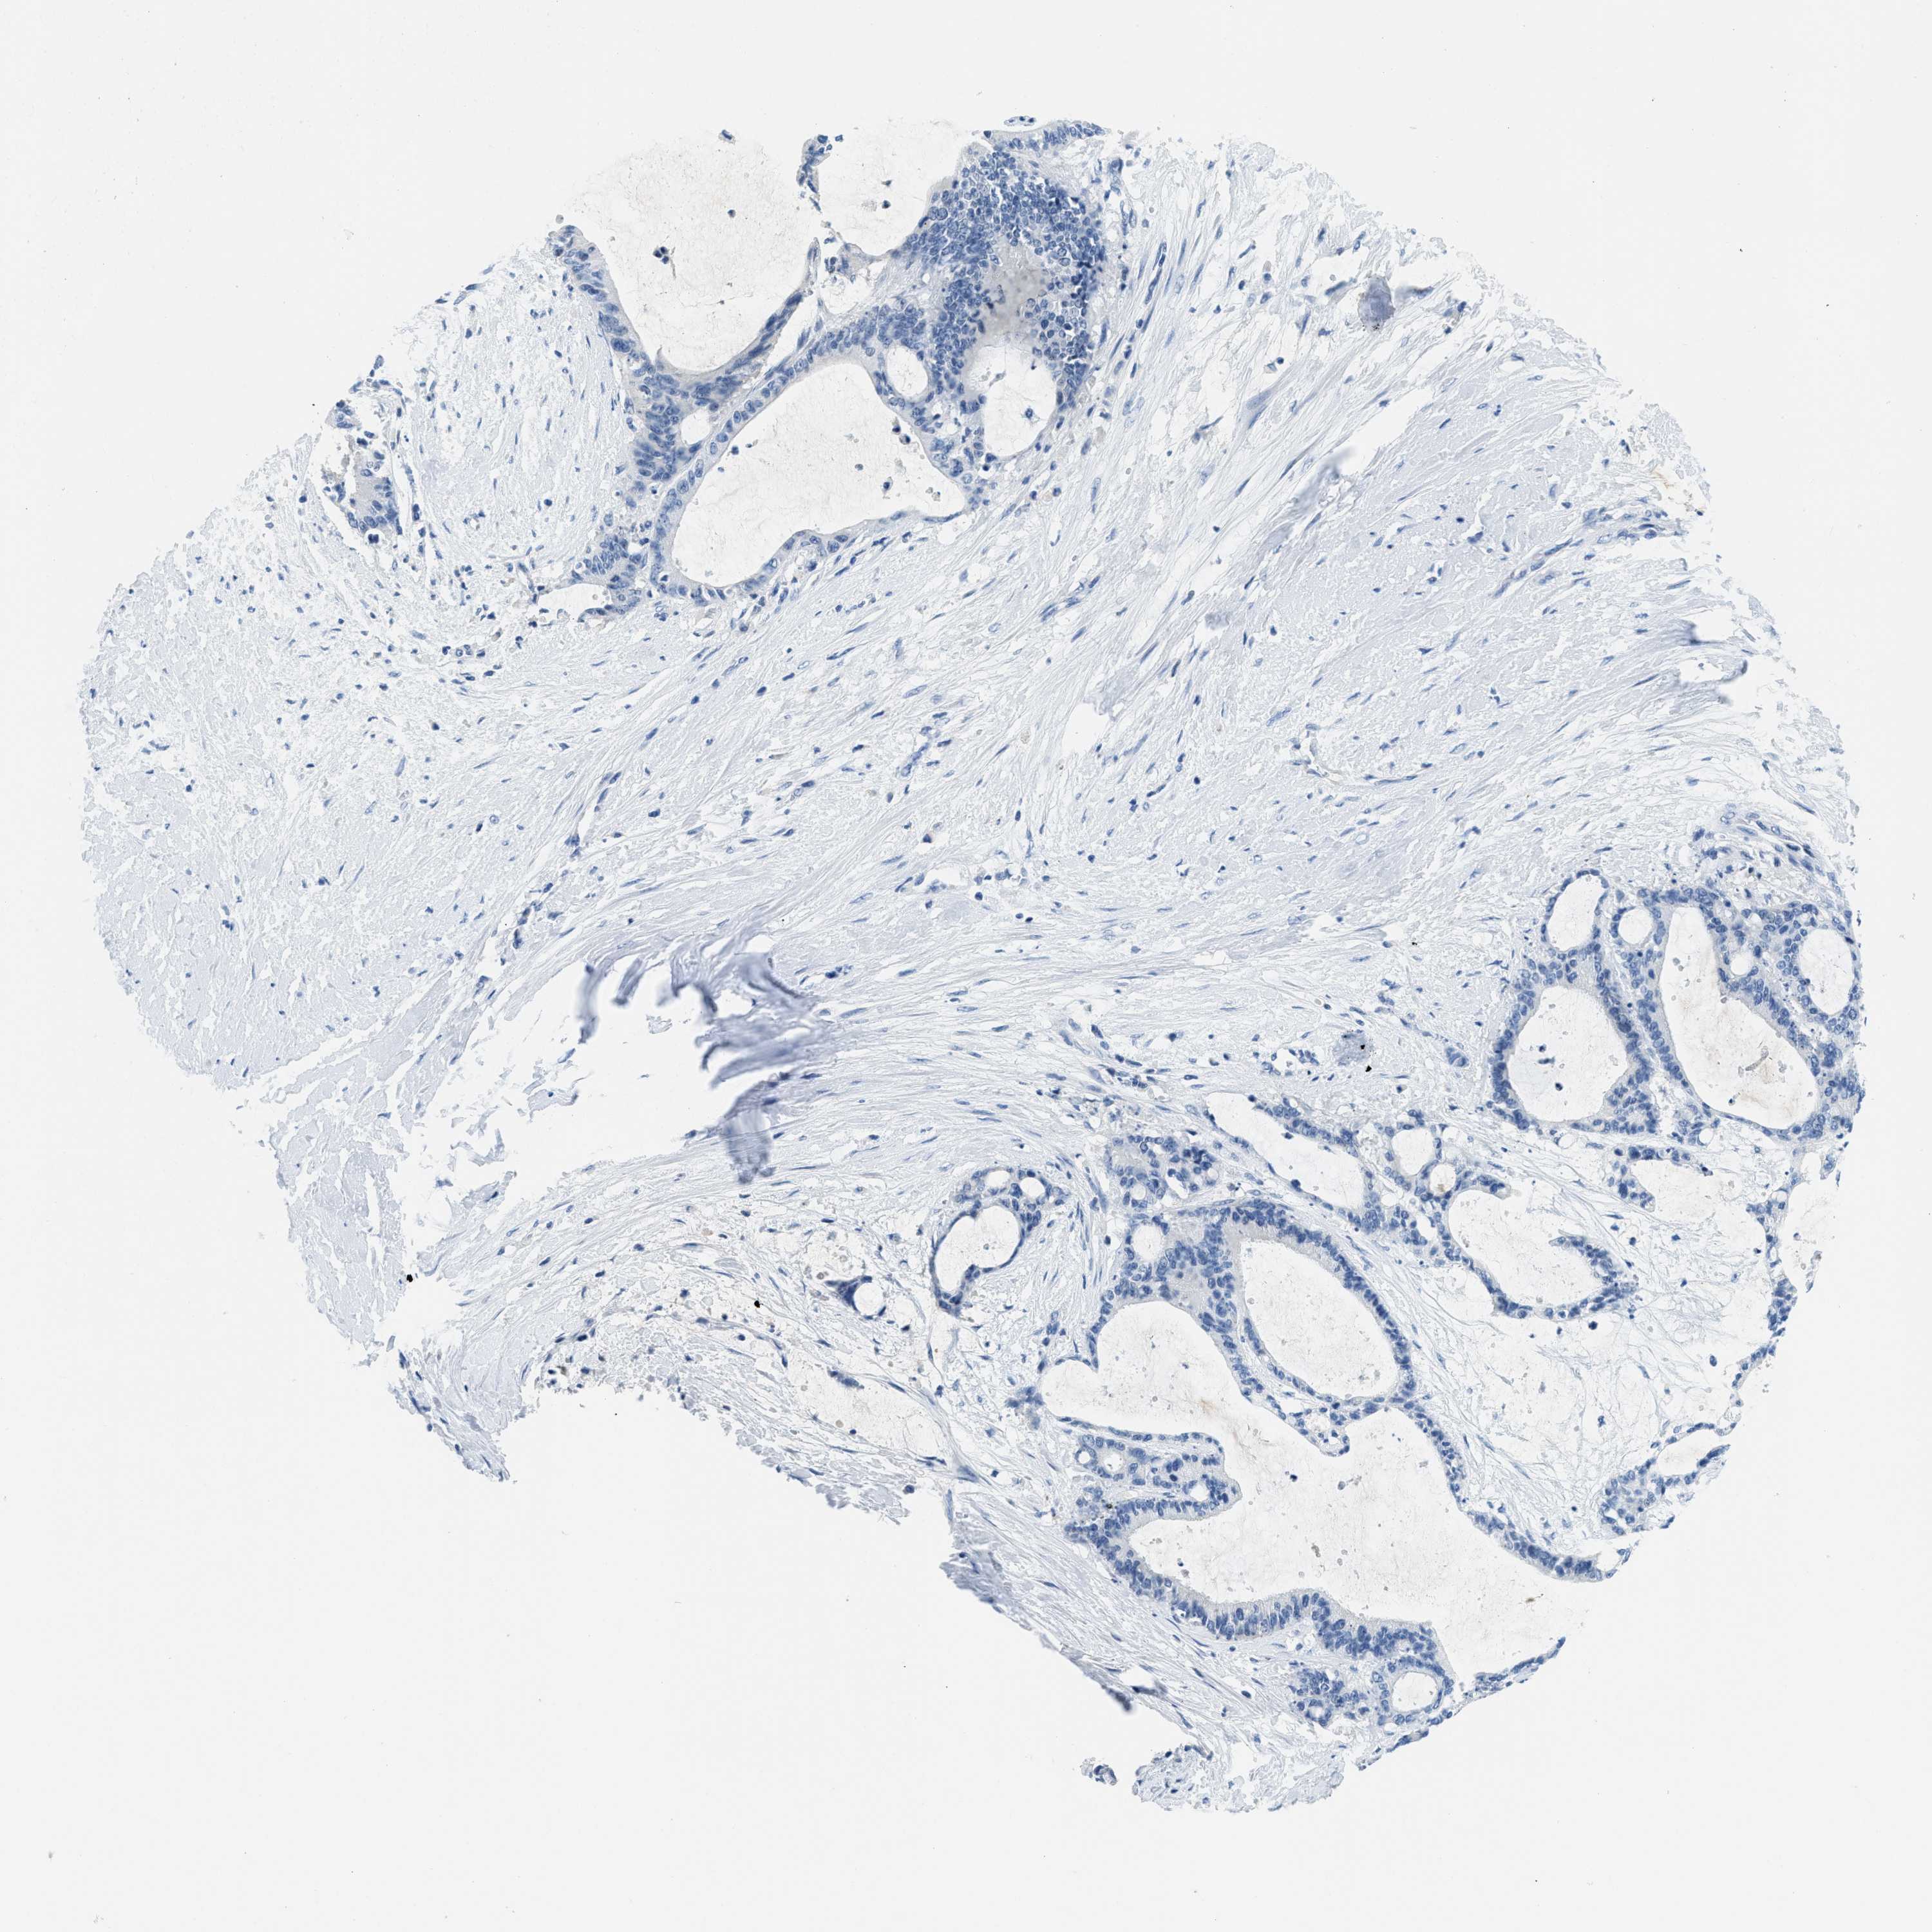

LIVER CANCER - Protein expressioni

A mouse-over function shows sample information and annotation data. Click on an image to view it in a full screen mode. Samples can be filtered based on level of antibody staining by selecting one or several of the following categories: high, medium, low and not detected. The assay and annotation is described here.

Antibody stainingi

Antibody staining in the annotated cell types in the current human tissue is reported as not detected, low, medium, or high, based on conventional immunohistochemistry profiling in selected tissues. This score is based on the combination of the staining intensity and fraction of stained cells.

Each image is clickable and will lead to virtual microscopy that enables deeper exploration of all samples and also displays staining intensity scores, fraction scores and subcellular localization as well as patient and tissue information for each sample.

Antibody HPA002027

Antibody CAB016782

Staining

High

Medium

Low

Not detected

Intensity

Strong

Moderate

Weak

Negative

Quantity

>75%

75%-25%

<25%

None

Location

Nuclear

Cytoplasmic/membranous

Cytoplasmic/membranous,nuclear

Carcinoma, Hepatocellular, NOS

Cholangiocarcinoma